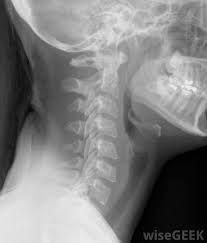

What Does Throat Cancer Look Like On An X Ray / Staging Of Laryngeal Cancer Using 64 Channel Multidetector Row Ct Comparison Of Standard Neck Ct With Dedicated Breath Maneuver Laryngeal Ct American Journal Of Neuroradiology / What does cancer look like in the throat?. Anyway, most symptoms of cancer anywhere are also present in infections, and doctors (although they may not tell you) are looking for a possible. Oral cancer is another name given to mouth cancers. Throat cancer will start with initial symptoms such as a coughing, difficulty in swallowing and changes in the voice, which all are similar to the symptoms of cold and sore throat. Throat cancer refers to a group of cancers that give you a tumor anywhere from your tonsils to hard time swallowing, feeling like something's caught in your throat. The most common sign of throat cancer is a sore throat.

The throat (also called pharynx) is a tube that runs from the back of the nose to your gullet (oesophagus) and the windpipe. Many people mistake throat cancer with cold or sore throat. Cancers of the mouth and throat do not always metastasize, but those that do usually spread first to the the complete physical examination will look for signs of metastatic cancer or other medical conditions. Throat cancer (laryngeal cancer) is a general term that usually refers to cancer of the pharynx and/or larynx how do health care professionals diagnose throat cancer? Where can you find the necessary information?

Mouth And Throat Cancer Ear Nose And Throat Disorders Merck Manuals Consumer Version from www.merckmanuals.com The throat (also called pharynx) is a tube that runs from the back of the nose to your gullet (oesophagus) and the windpipe. The cause of the tightness can vary from an infection like strep throat to a more serious allergic. Though most throat cancers involve the same types of cells, specific terms are used to differentiate the part of the throat where cancer originated. Where can you find the necessary information? Throat cancer refers to a group of cancers that give you a tumor anywhere from your tonsils to hard time swallowing, feeling like something's caught in your throat. Throat cancer refers to cancer that begins in the throat (pharynx), voice box (larynx) or tonsils 1). Mouth and throat cancer surgery. Like all head and neck cancers how do doctors diagnose throat cancer?

Sometimes, it can cause a palpable lump to form in the neck, although this symptom is not always present. Oral cancer is another name given to mouth cancers. Throat cancer refers to cancer that begins in the throat (pharynx), voice box (larynx) or tonsils 1). What foods do you like? Also, people who smoked for less than 10 years may do better. How many meals a day do you have? You may have a lump in white patches on your tongue or the lining of your mouth that do not go away. Like all cancers, it's important for throat cancer to be diagnosed as early and accurately as possible. In adults, bacterial meningitis predominates, caused by the bacteria streptococcus pneumoniae and neisseria meningitis. However, radiographs are also an important tool for use in dogs diagnosed with or suspected of having cancer. If there is a scratch on your knee put iodine on it. Your doctor can do an intensive physical examination. Beams are directed at the tumor and affect only the projection area.